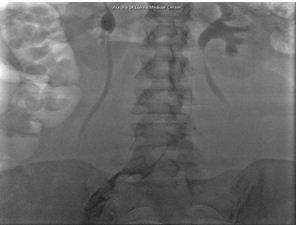

Residual thrombus (Figure 1) was noted in the origin of the left common iliac vein shortly after the procedure and required extensive catheter-directed infusion of tissue plasminogen activator. The following day additional mechanical thrombolysis was performed and the patient underwent post-procedure evaluation with intravascular ultrasound. A persistent round filling defect was noted at the inferior vena cava bifurcation with near complete occlusion of the right common iliac vein. There was progressive recurrence of thrombus in the left iliac venous system (Figure 2) and involvement of the right lower extremity, where a new clot was noted.

Figure 2